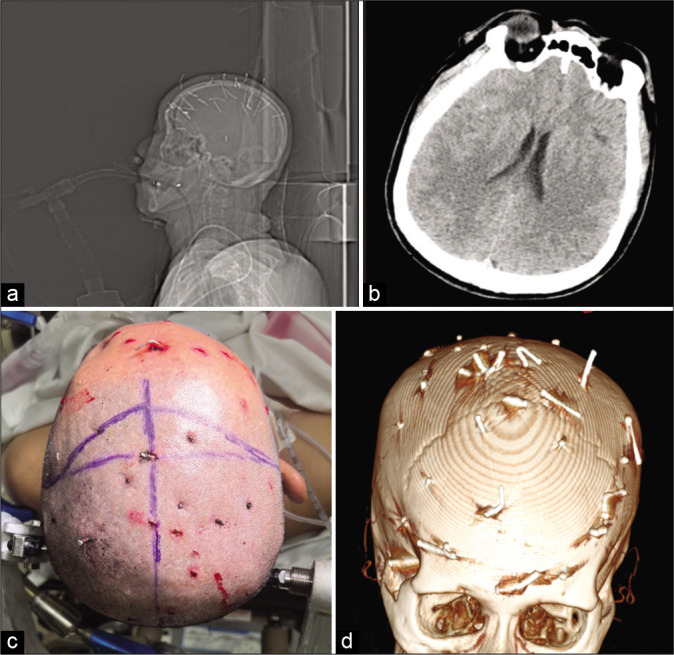

Figure 1:

Representative images at patient presentation. (a) Scout skull X-ray showing all 32 nails, (b) CT axial showing no midline shift at time of presentation, (c) head with patient positioned and incision marked, and (d) stealth scan model used intraoperative.